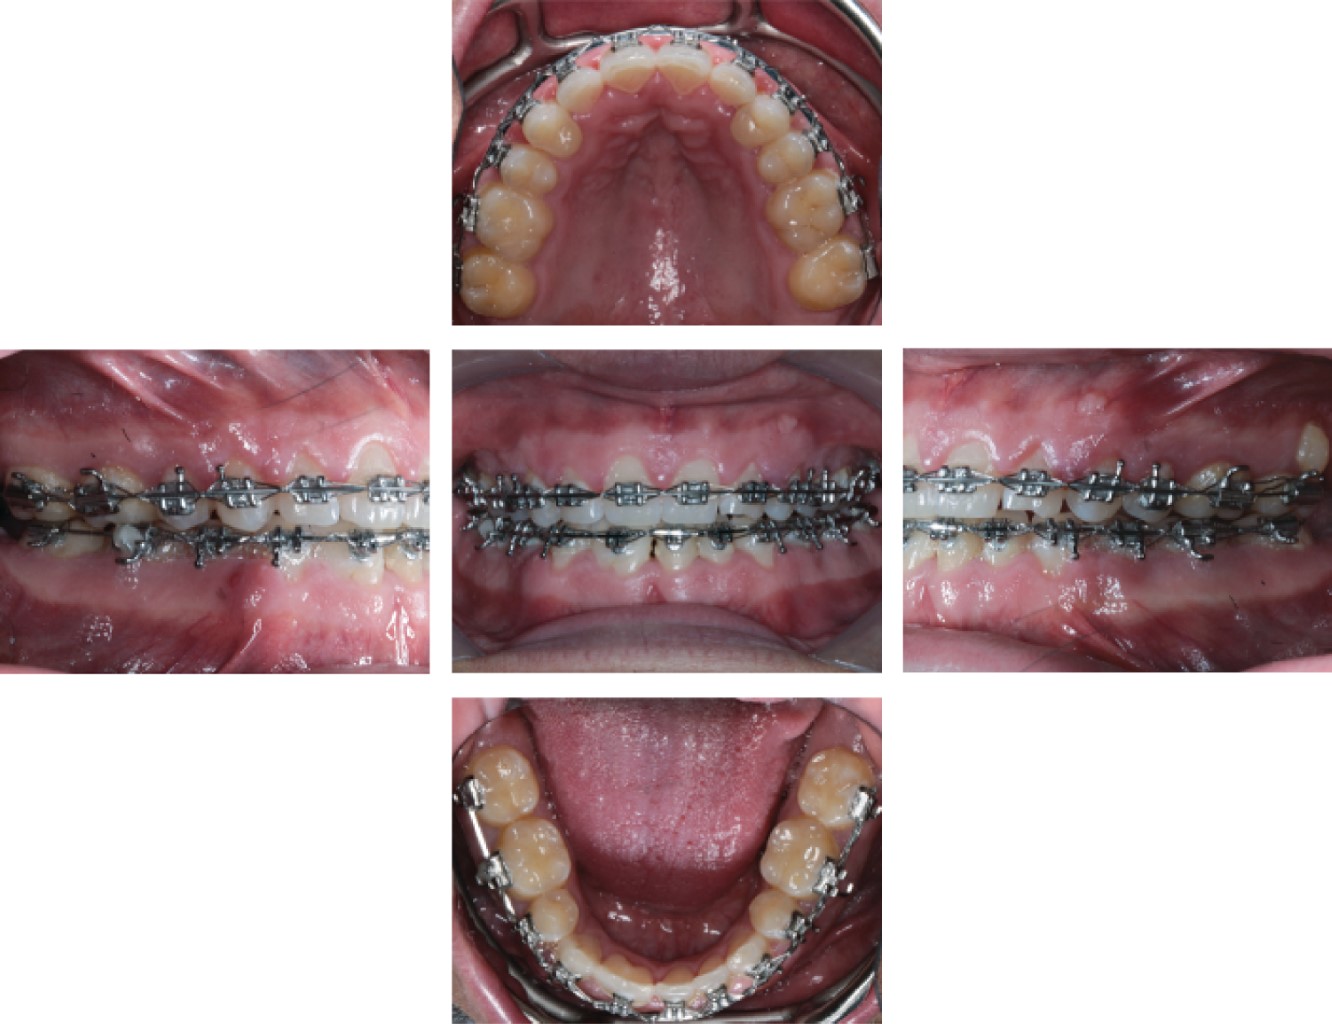

Para el presente caso, se utilizaron brackets Synthesis de la casa comercial ORMCO con prescripción Roth (slot 0.022) para potenciar el torque y la expresión de los arcos, utilizando una secuencia para la etapa de alineación y nivelación de 0.014 Cuniti®, 0.016 Cuniti®, 0.0 18 Cuniti® y 0.017 × 0.025 Cuniti®. En esta etapa inicial, se decidió realizar extracciones de los órganos dentales 34 y 44 para reducir la discrepancia óseo-dentaria de la arcada inferior, aumentar el overjet y overbite. Una vez concluida la etapa I, se decidió pasar a la segunda etapa de cierre de espacios y realizar una mecánica de cierre recíproco por medio de cadenas elásticas, en donde al cerrar los espacios de ambas arcadas se llevó una secuencia de arcos de 0.017 × 0.025SS y 0.019 × 0.025SS (Figura 5). Al concluir la etapa de cierre de espacios, se procedió a realizar ameloplastias negativas en cúspides palatinas de órganos dentales 14 y 24, los cuales, por cuestión de las anodoncias de los órganos 13 y 23, se decidió que cumplirían con la función de los órganos dentales ausentes mencionados debido a que presentaban buenas características de soporte como una buena longitud radicular y una base ósea adecuada. Además, la posición de los primeros premolares superiores quedo adecuada para establecer una buena relación canina. Una vez realizadas las ameloplastias negativas, se procedió a realizar ameloplastias positivas en los mismos órganos dentales por medio de agregados de resina compuesta para dar una adecuada morfología cuspídea, para que estos órganos puedan realizar adecuadamente la función de guías caninas, lo cual fue uno de los objetivos de tratamiento principales. Al concluir con estas etapas, se procedió a realizar la etapa final en donde se colocaron arcos Braided 0.019 × 0.025 para favorecer el asentamiento de mordida. Se dieron indicaciones de realizar ameloplastias positivas con agregados de resina en dientes afectados por la atrición

Figura 5